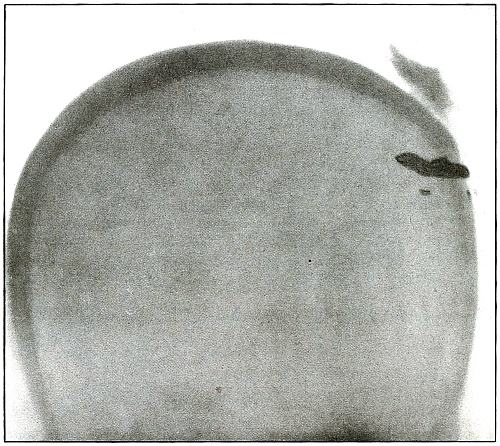

Plate 1.

[Pg 13]

Rifle—Plate 1.

HEAD.

Gunshot Fracture of the Skull,

with Lodgment of the Missile.

The bullet in this case was so badly deformed by ricochet that

part of both core and jacket were lost. While the appearance of the

shadow seems to indicate a direct impact of the nose of the bullet,

the line of contact with the skull must have been tangential, with

some laceration of the scalp; otherwise a cursory examination of the

scalp wound would have revealed the slightly protruding end of the

bullet. The dark shadow above the projectile is due to material used

in dressing. The great thickening of the scalp in the region of the

wound shows a marked cellulitis. Small particles of the lead core of

the bullet can be seen about the wound.

In such cases there is often a marked infection of the scalp

without extension of infection to the cranial cavity, except from

neglect. This is a case, though apparently simple, in which the

radiograph was necessary for correct diagnosis without exploration.

The treatment in such cases is conservative, with removal of

the projectile and care of the superficial infection or subsequent complications.